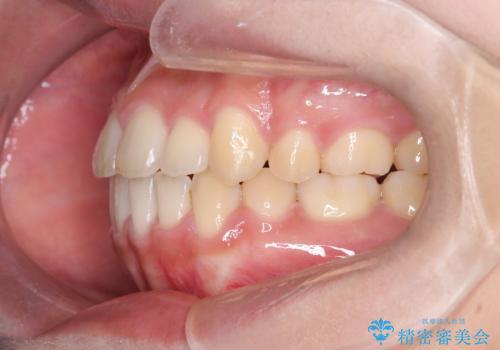

- 八重歯と口元が出ていることを主訴に来院されました。

レントゲンの検査において、前歯も外側に傾いてる結果であったため、上下左右の小臼歯を抜歯して配列を行いました。

歯の動きも良く短期間で治療を終えられたため患者さんにも大変満足していただきました。